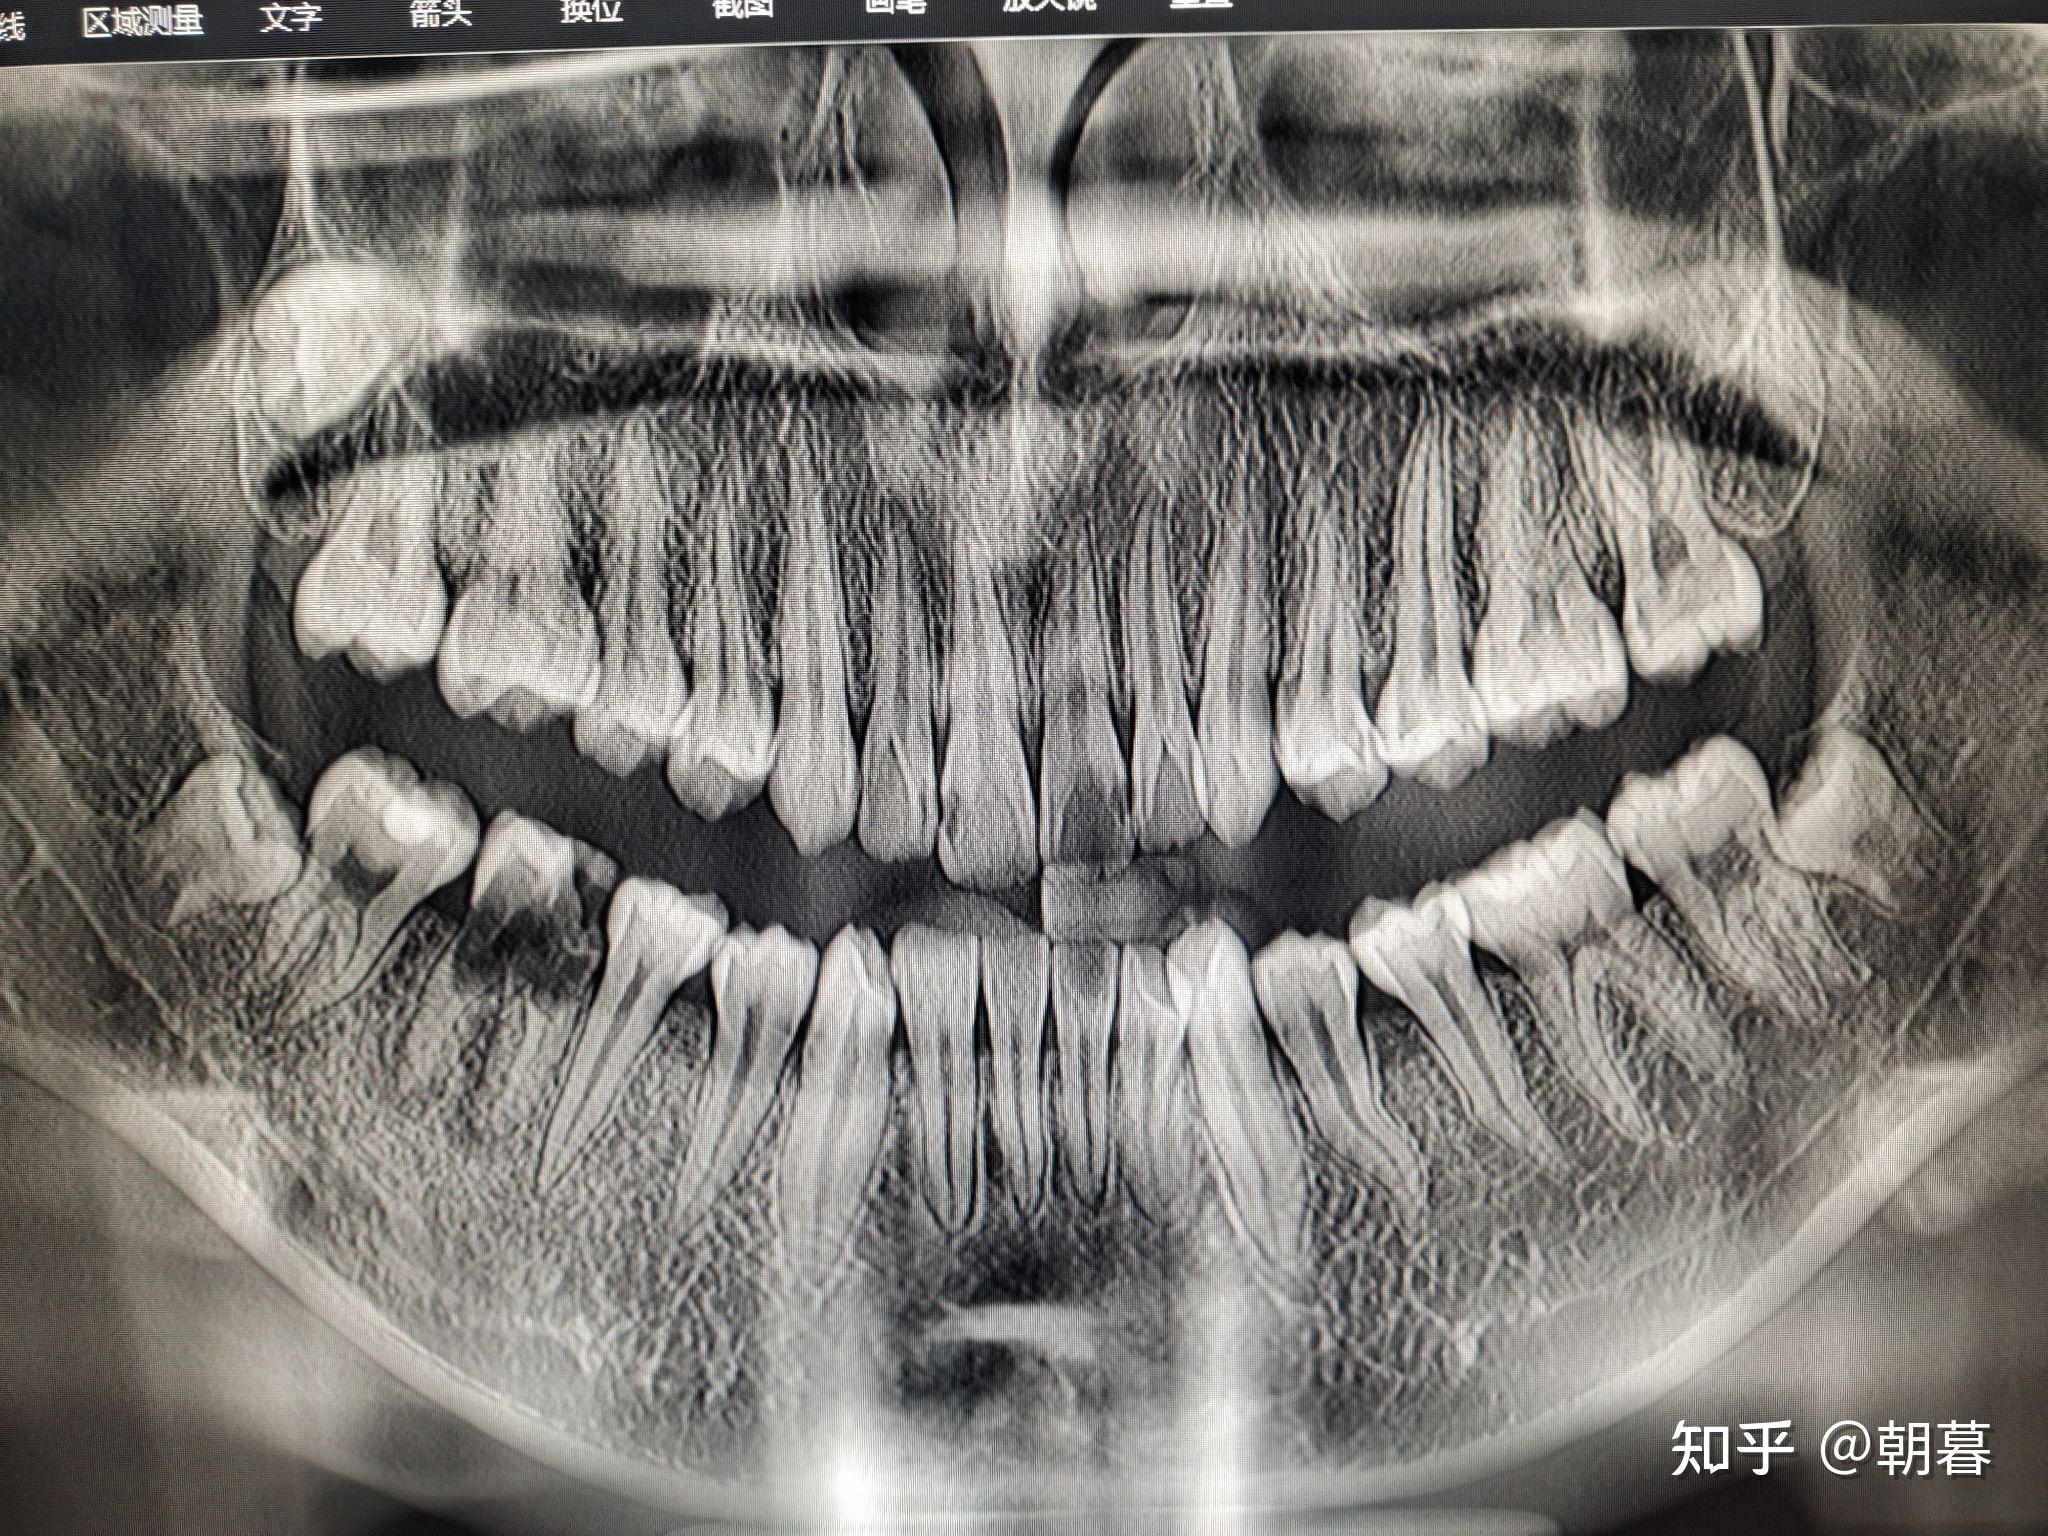

换牙期小朋友的牙片可以清楚看到有四排牙齿 (还有两颗是长在眼睛下方